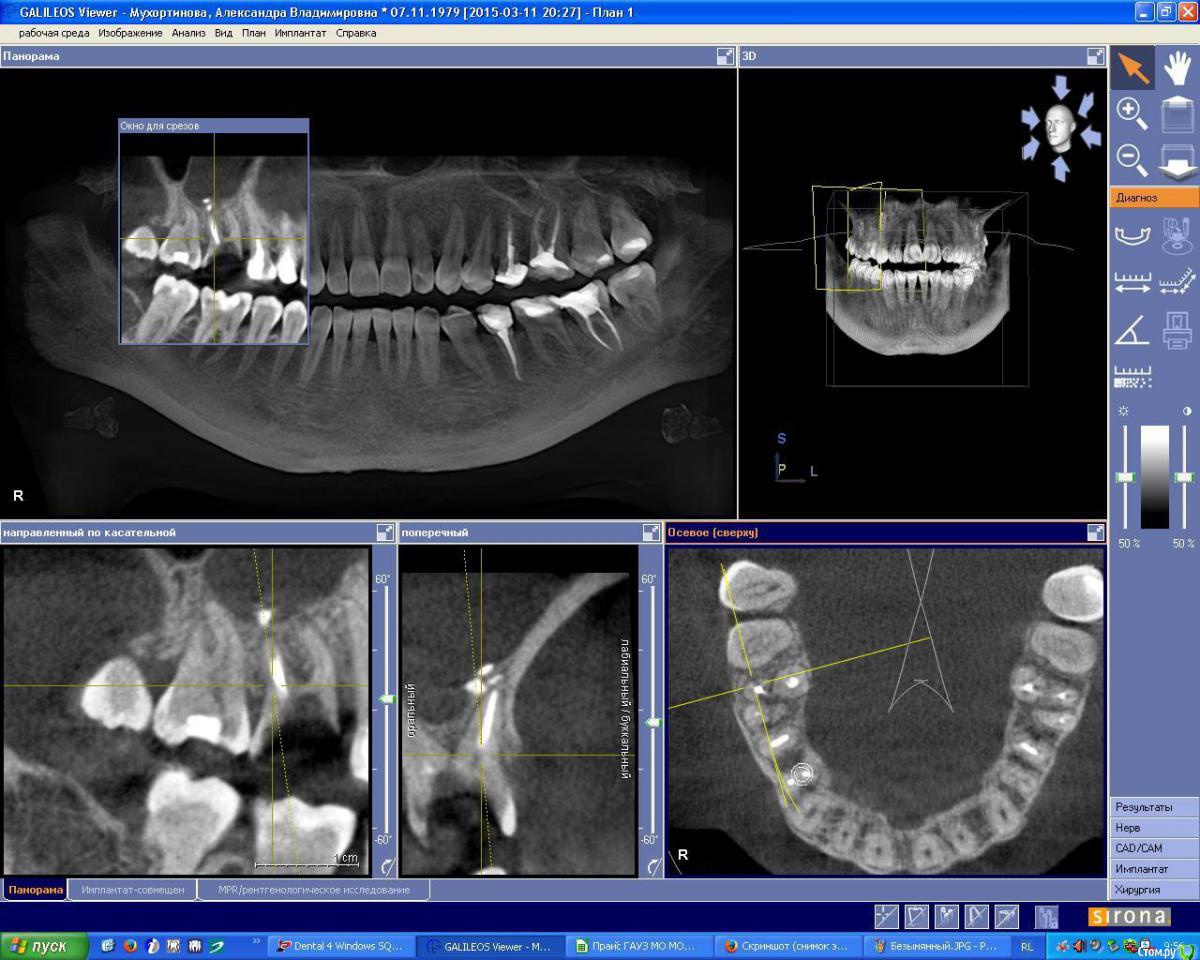

IshIm0 Опубликовано 8 июля, 2015 Поделиться Опубликовано 8 июля, 2015 (изменено) Добрый день. Пациентке Н. 2 недели назад ЛОР-врач удалил инородное тело из гайморовой пазухи справа (пломбировочный материал), который мигрировал в подглазничную область. Сейчас необходимо удалить зуб 16, пациентка хочет имплантат в последующем.Как всё правильно сделать ? Я думаю атравматично удалить зубик, аккуратно вычистить оставшийся пломбировочный материал в проекции дистально-щечного корня зуба 16 через лунку, подсыпать ксенокость, укрыть резорбируемой мембраной, через пол года установить имплантат в проекции 16 с одномоментным синус-лифтингом. Изменено 8 июля, 2015 пользователем IshIm0 Ссылка на комментарий

OLG Опубликовано 8 июля, 2015 Поделиться Опубликовано 8 июля, 2015 есть кистогранулёма в бифуркации Нет там кистогранулемы в фуркациия вижу резорбцию костной ткани по бифуркации.обычно резорбция костной ткани в бифуркации сопровождается наличием грануляционной ткани или кисты. (см. снимки 1 и 2) 1 Ссылка на комментарий

IshIm0 Опубликовано 16 июля, 2015 Автор Поделиться Опубликовано 16 июля, 2015 (изменено) Что же ЛОР сказал об остальной части пазухи? Как-то по снимкам там не очень хорошо...Снимки до операции у ЛОР врача, предполагаю, что на инородное тело так слизистая отреагировала, да и на инфицированный зубик. В итоге удалил зуб -> сгусткок -> тонкая коллагеновая губка -> X-образный фиксирующий губку шов.В бифуркации разрастание грануляционной ткани было.Всем спасибо за советы. Изменено 16 июля, 2015 пользователем IshIm0 Ссылка на комментарий